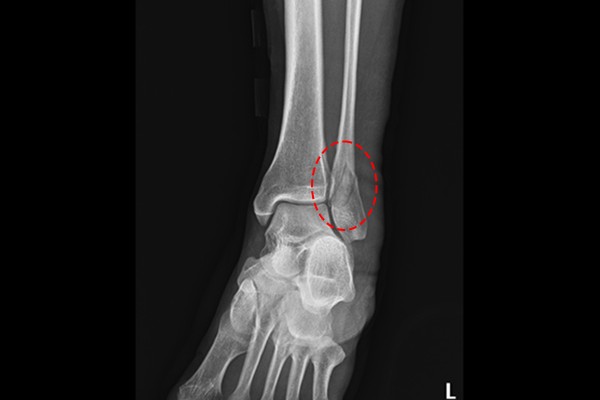

42세 여성 환자분께서 좌측 발목 통증으로 내원해주셨습니다. 내원 전날 길을 걷다가 미끄러지면서 다치셨고, 근처 타병원을 들렸을 때, 추후 후유증이 있을 수 있다고 하여 수술 권유를 받으셨고, 검색을 통해 골절 수술 병원, 정형외과인 저희 병원을 찾아오셨다고 말씀하셨습니다.

환자분의 발목 상태를 확인하기 위해 촬영한 X-RAY 검사에서 발목 외측복사(복숭아뼈)부분에 골절선이 명확하게 확인되었고,